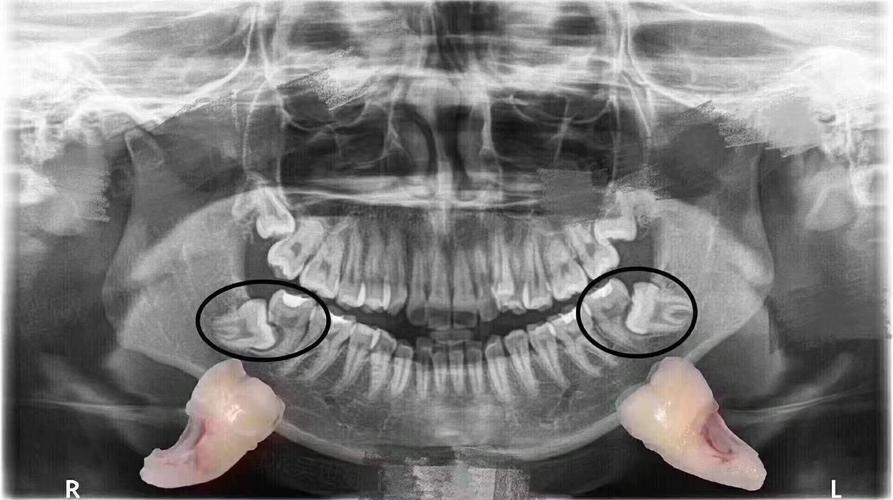

小孩牙齿x光图,小孩牙齿图片恒牙图片

看牙齿的x光片如何看出牙齿是恒牙还是乳牙?

牙齿的牙根是埋在牙槽骨中的 医生没有透视眼 为了解患牙的牙根的

没换牙的小孩的x光图

正常儿童牙齿x光图

儿童换牙x光图